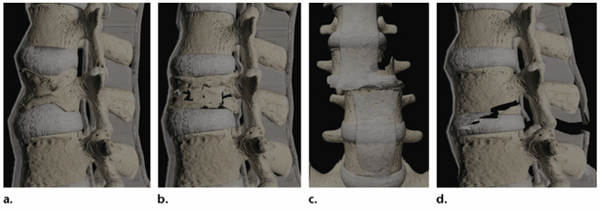

Механизм травмы:

- a. Компрессия/ (простая компрессия)

- b. Взрывная компрессия

- c. Поступательный/вращательный

- d. Дистракция